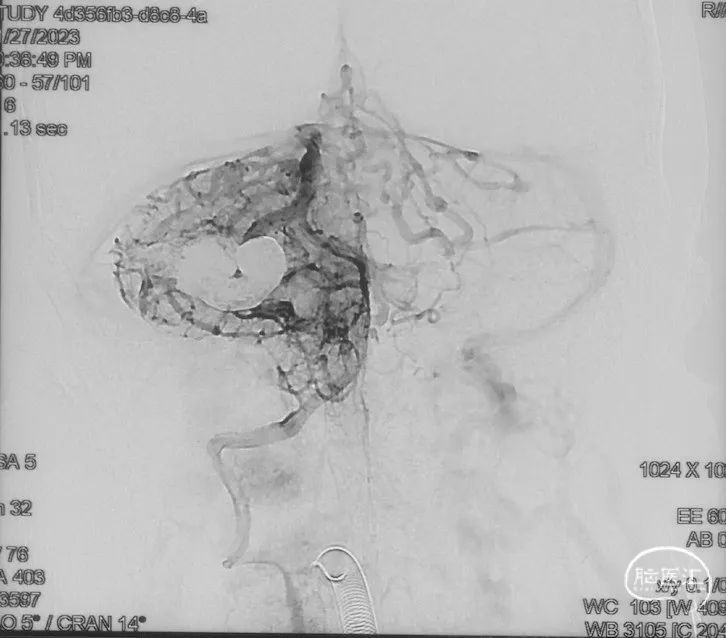

术前造影

证实为TDAVF,为岩上窦型。R-ECA正侧位见右侧脑膜中动脉分支、枕动脉分支、颞浅动脉分支向瘘口供血,经幕上迂曲扩张的静脉、中脑周围静脉、基底静脉向深部静脉引流。

R-ICA正侧位见右侧脑膜垂体干向瘘口供血

L-ICA正侧位见左侧脑膜垂体干分支向瘘口供血

L-ECA正侧位未见向瘘口供血

L-VA、R-VA正侧位右侧小脑上动脉脑膜支向瘘口供血

结构分析:右侧天幕区硬脑膜动静脉瘘,瘘口位于右侧岩上窦,供血动脉主要包括右侧脑膜中动脉的颞支、岩鳞支,右侧枕动脉分支,右侧颞浅动脉分支,双侧脑膜垂体干,右侧小脑上动脉脑膜支,经幕上迂曲扩张的静脉、中脑周围静脉、基底静脉向深部静脉引流,引流静脉起始部见扩张的静脉球。Cognard分型IV型,Borden分型III型,Lawton分型IV型(岩上窦型)。

选取工作角度,正侧位造影